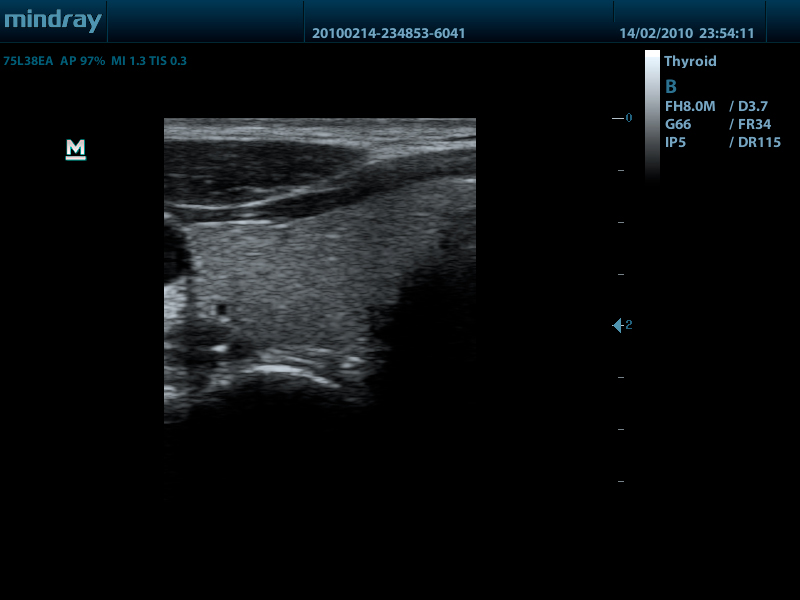

- Линейный датчик 75L38EA, 3.3 - 13.0 МГц, апертура 38 мм